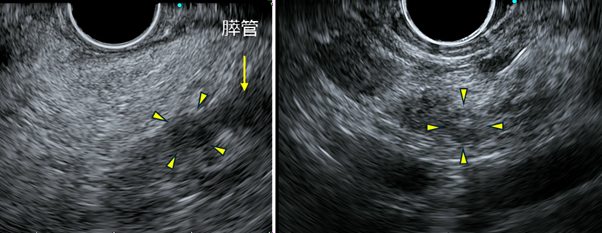

そこで、EUSを行いました。EUSでは、拡張した膵管を途絶するところに、約7mmの小さな低エコー腫瘍(黄色矢頭)を認めました。膵癌の疑いとして、EUS-FNAを行ったころ、腺癌の診断となりました。

EUS所見

左:膵管と途絶する場所に、7mm大の低エコー腫瘤を認めます。

右:この腫瘤に対して、専用の針を用いて穿刺しました。